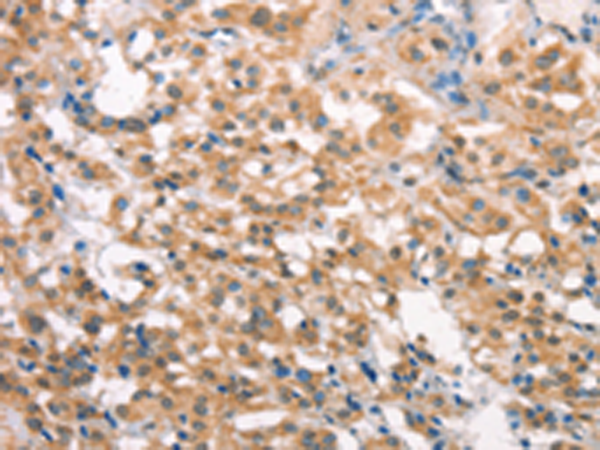

分类: 科研抗体货号: P11213别名: KPM应用: IHC反应种属: Human, Mouse